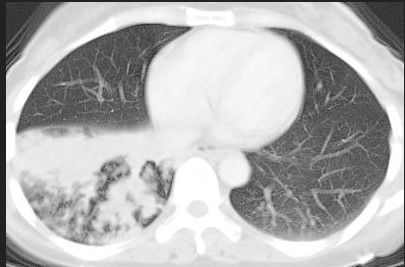

阻塞性肺炎是临床上较为常见的肺部感染性疾病之一,是在支气管腔堵塞或狭窄的基础上继发感染后呈现的X线表现。既不同于一般肺炎,也不同于肺不张,病因众多、治疗方法各异。因此,及时明确病因,对选择治疗方法非常重要。

阻塞性肺炎的病因较多,比如肺结核、肿瘤等,各自有相应的体征及辅助检查结果。血常规可见白细胞升高。若影像学检查提示两上肺阻塞多以肺结核为主,两下肺阻塞则以肺部肿瘤为主。胸片等影像学中良恶性阻塞性肺炎的形态有时候非常相似,容易误诊,为了更好鉴别两种,要仔细询问病史,认真做好体格检查。必要时可以在B超或CT引导下肺肿块活检穿刺术或胸腔积液做生化、肿瘤标志物、组化免疫学和做细胞学、组织学等病理学确诊。